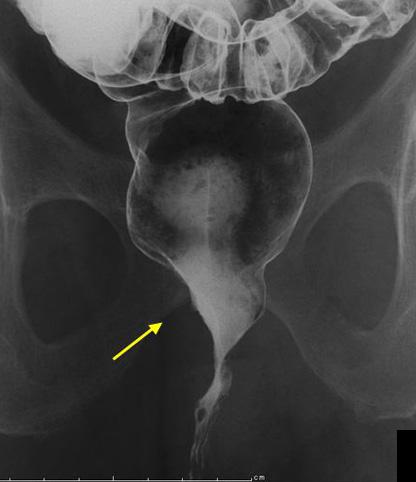

症例提示(所在地,施設名等): 大分県・ 中津市民病院 (石橋先生からの提供症例)

症例登録日 2008/12/19

性別 男性

年齢 70-74

疾患(病理主体)の分類悪性上皮性腫瘍/その他

部位(臓器別)大腸/直腸

検査方法X-P

腫瘍の肉眼分類5型(分類不能)/

病変の最大径(ミリ)35〜40

腫瘍の深達度s(a)